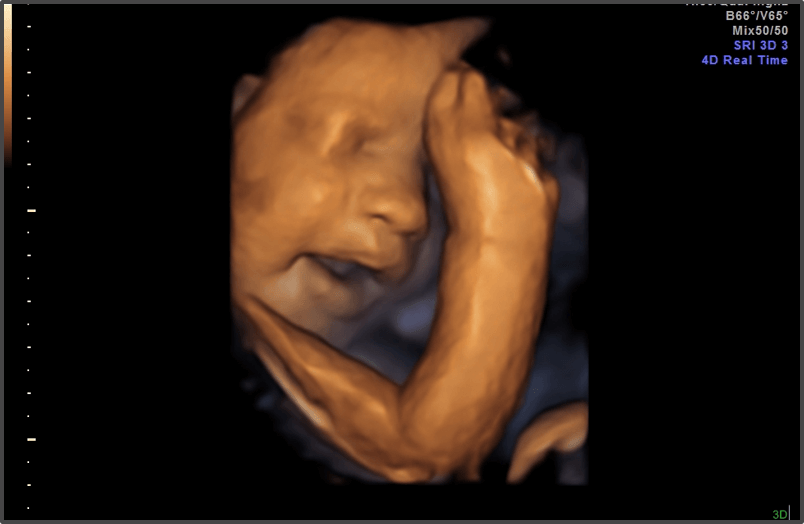

Your baby is the size of a coconut.

Approx Baby Weight: 1.5kg

Approx Baby Size: 41.1 cm

Baby Development

The baby’s bones and muscles are becoming more defined.